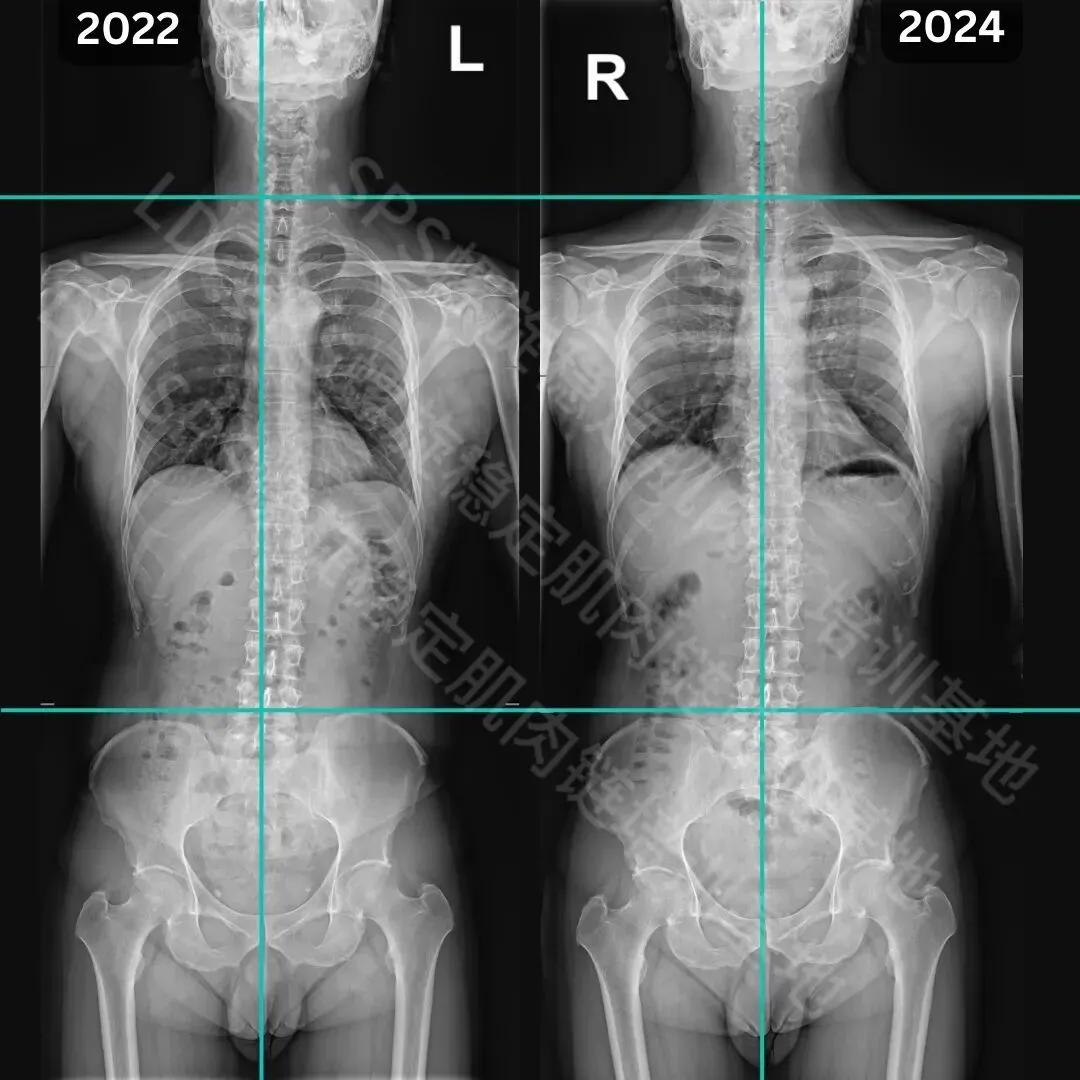

成年人侧弯改善案例

经过6个月的SPS螺旋稳定肌肉链训练

弯度数改善5度;2.右侧肩胛骨的位置明显改善;3.肩胛骨下角周边肌肉通过锻炼得到强化。